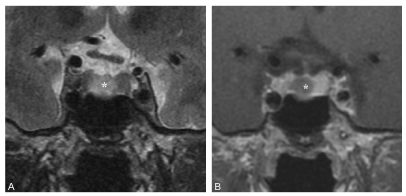

Le microadénome se présente sous la forme d’une lésion arrondie de petite taille (< 10 mm) siégeant souvent dans la partie latérale de l’antéhypophyse, sans ou avec peu d’effet de masse sur celle-ci (figure 51.1). Il présente parfois un hypersignal en T2 bien visible et prend le contraste de façon moins intense que l’hypophyse normale.

Fig. 51.1. Microadénomes hypophysaire.

IRM en coupes frontales centrées sur la région hypophysaire pondérées en T2 (A) et en T1 après injection de gadolinium (B). Formation arrondie intrasellaire latéralisée à droite (∗) en hypersignal en T2 et prenant moins le contraste que l’hypophyse saine.

Source : CERF, CNEBMN, 2022.